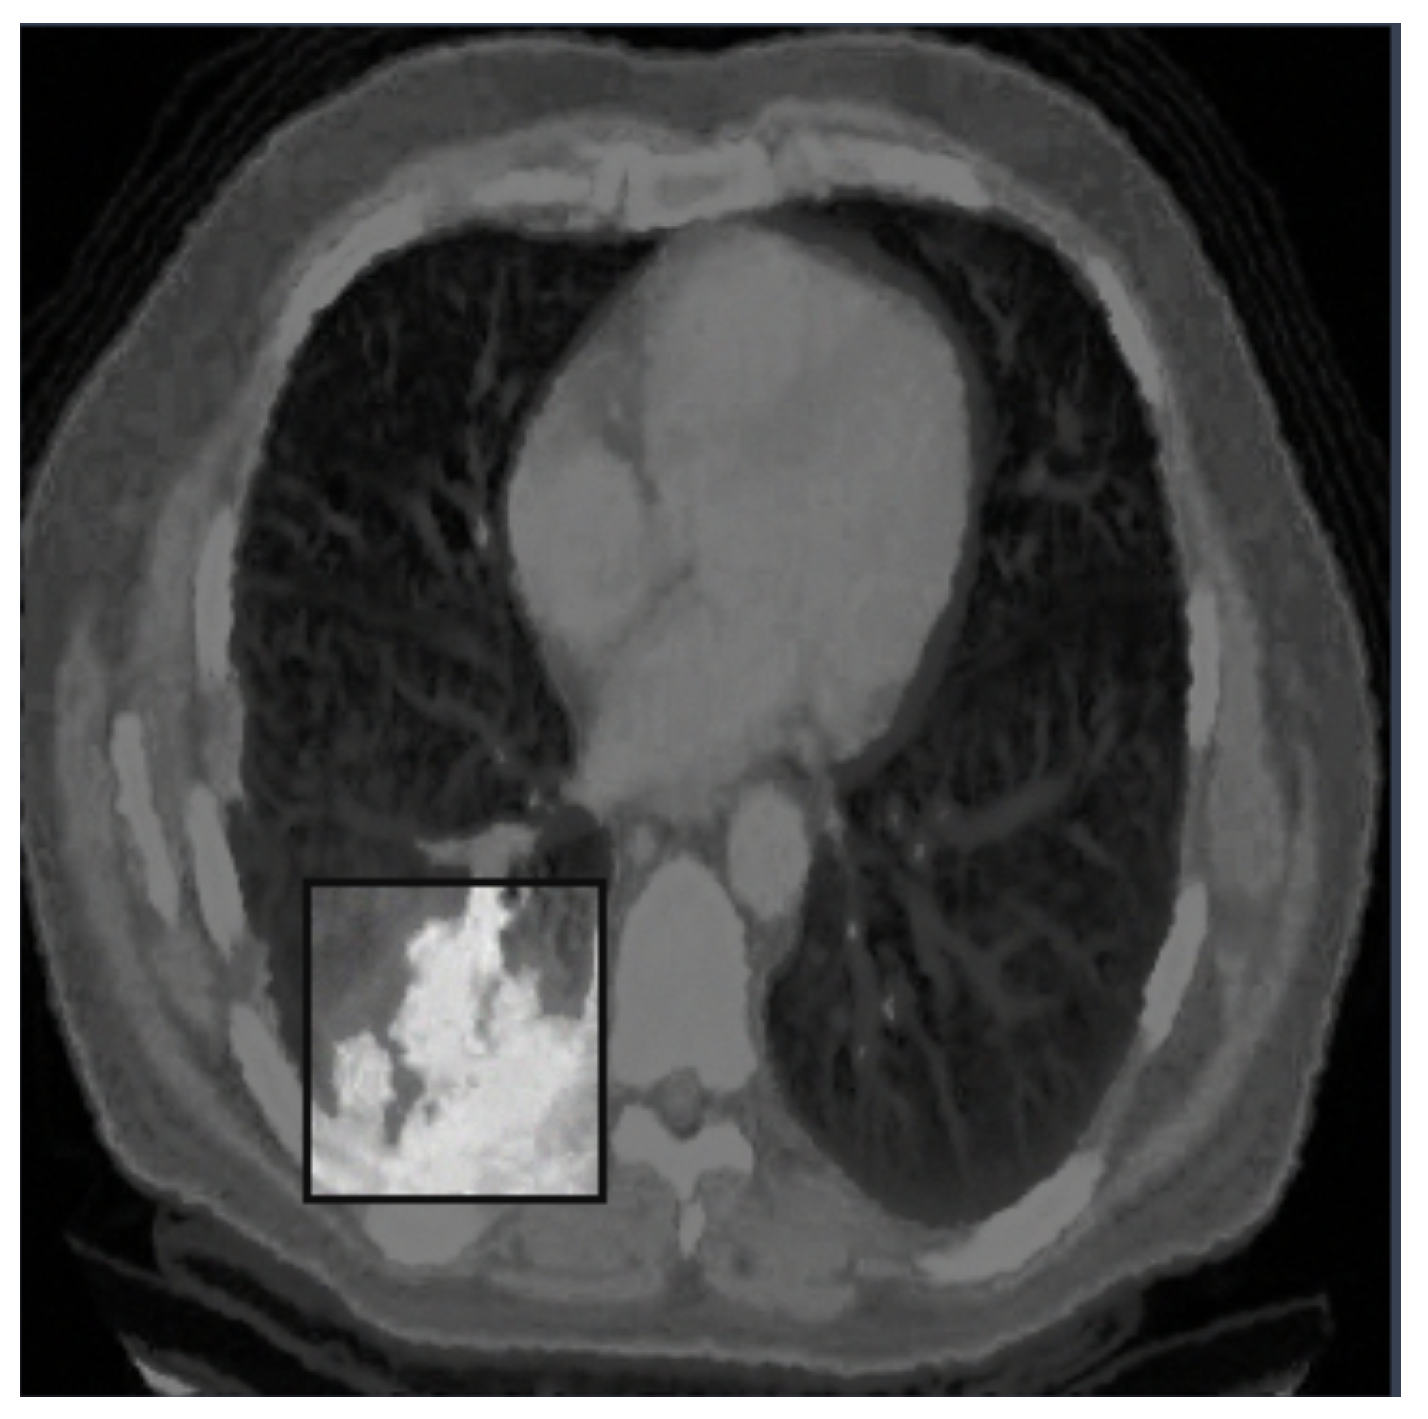

4. Experimental Analysis